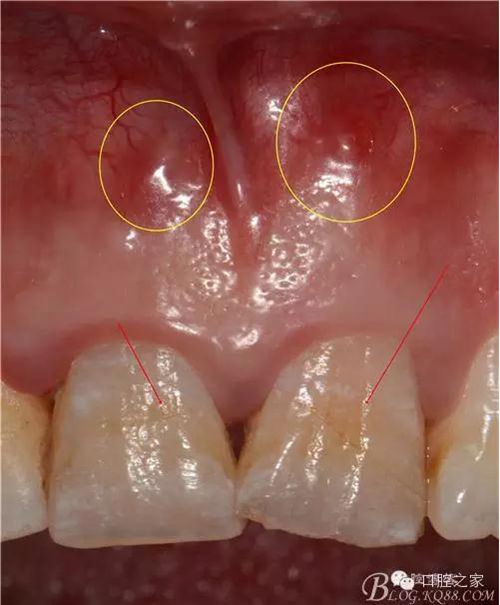

根管內(nèi)因素治療失敗,查清原因后重新治療,大都可以治愈。根管外因素所致失敗,除部分病例配合外科可以治愈,大多數(shù)病例重新作根管治療也難以成功,形成真正的難治性根尖周炎。筆者在《實用牙髓病診療學(xué)》中將竇道口形狀分為6種,其中的膿性針眼狀竇口(壓有白色膿液溢出,竇口僅有針眼大小無突起)幾乎都是根管外原因,單純根管治療難以奏效。

1.根尖吸收或未形成 嚴(yán)重的慢性根尖膿腫可引起根尖吸收,X線片上可見牙根較正常牙短。治療時因根尖狹窄處消失,擴大針深入到根尖處無明顯的阻力感;根管沖洗后滲出液不易吸干,經(jīng)多次封藥滲出液亦未能消失;拔除患牙可見根尖呈蟲蛀狀缺損(圖)。也可見于根尖未形成即因故感染的病例。